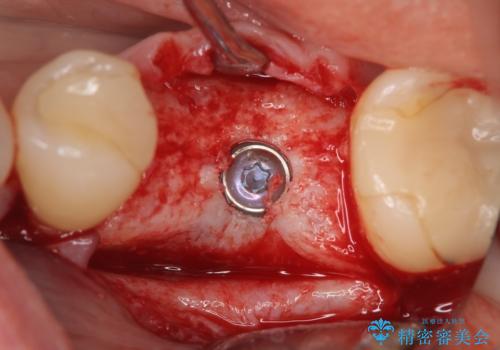

被せ物を外したところ歯が割れており保存不可能だったため抜歯し、インプラントによる欠損補綴を行いました。

当院では主にストローマンという種類のインプラントを治療に用いています。

ストローマンは世界的にもNo1のシェアを誇り、骨との適合にも優れたインプラントです。

カスタムアバットメントは患者様それぞれの歯茎に合わせて製作されたオーダーメイドのアバットメントです。

既製のアバットメントに比べ適合がよく、高い清掃性を誇ります。